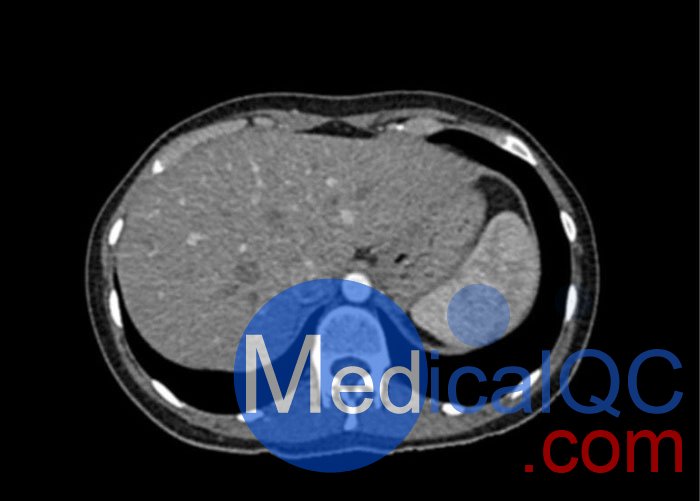

WEK53-01腹部模體,WEK53-01動脈期腹部模體,WEK53-01腹部模型模擬了動脈期的造影劑增強腹部。它覆蓋了第十一胸椎至第四腰椎(部分包括在內)。

該模型可用于 CT(包括 CBCT)以評估和優化成像性能和后處理應用,包括支持 AI 的應用。它也適用于培訓目的。

該模型提供了對軟組織和骨組織的詳細而逼真的模擬。空隙中填充著約-160HU的纖維素-聚合物復合材料。